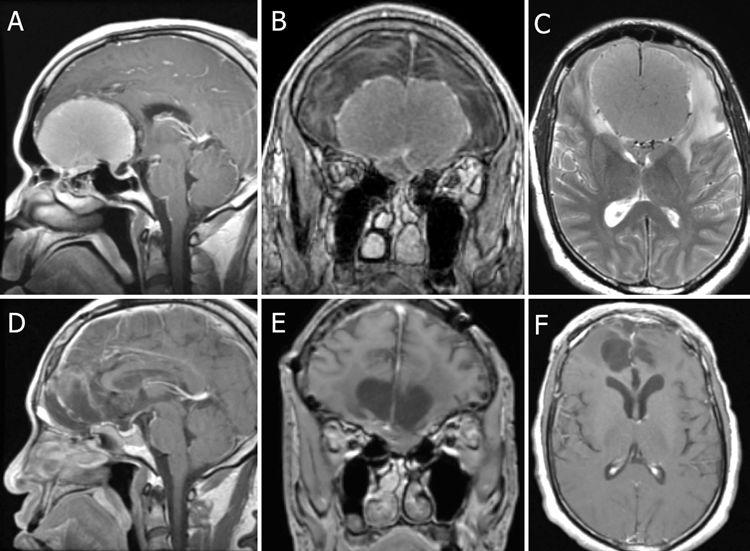

图4. 为图3患者,在30°内镜下经鼻入路切除OGM。A.在前颅底(ASB)腹侧作锁孔小骨窗切除颅底骨质,矢状面上从额窦(FS)后到蝶骨平台、冠状面上从左侧筛骨眶板到右侧筛骨眶板形成骨窗,电凝ASB硬脑膜使肿瘤血管闭塞;B、C.打开硬脑膜,先作肿瘤内部分块切除,再沿边界将肿瘤(T)小心地从额叶上分离;D.肿瘤切除后,额叶(FL)留下的空腔;E.用人工硬膜放置在颅底硬膜缺损处;F.将带血管蒂的鼻中隔粘膜瓣(NSF)旋转并覆盖颅底缺损处;粘膜瓣上做一个松弛的蝶形切口(箭头)以增加前后伸展度,向前到额窦的后表面和向后到蝶骨平台完整覆盖,保持血管蒂血流通畅;重建颅底。